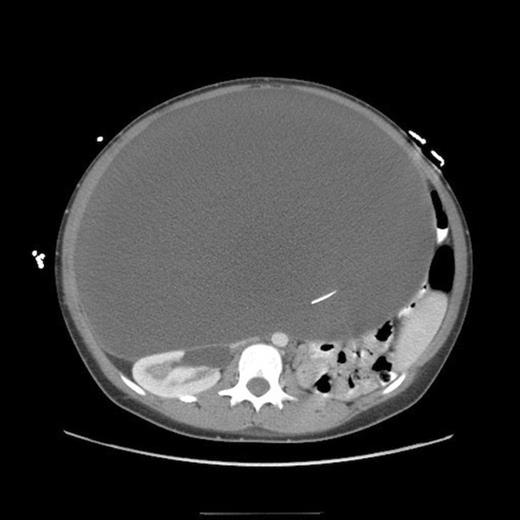

Abdominal CT, axial view, demonstrating a large fluid compartment surrounding the VP shunt catheter resulting in mass-effect, hydronephrosis, and displacement of the intra-abdominal contents

She eventually sought medical attention when she began developing diffuse, unremitting bilateral lower quadrant pain as her abdomen continued to enlarge (Fig. 1). A urine pregnancy test on admission was negative. Abdominal CT demonstrated a large fluid compartment surrounding the VP shunt catheter resulting in mass-effect, hydronephrosis, and displacement of the intra-abdominal contents (Fig. 2 and 3), establishing a diagnosis of APC.